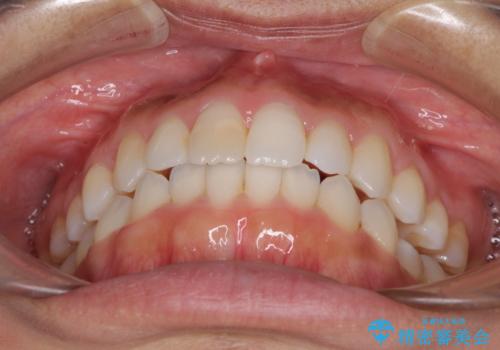

前歯の叢生を治したい インビザラインによる矯正治療

- 上下の前歯のデコボコと奥歯の反対咬合を気にして来院された患者様です。

インビザラインを用い、上下顎ともにIPR(歯と歯の間を削る)により叢生を改善することとしました。

奥歯の反対咬合は、骨格に由来するものであるため、改善できるところまで改善していくこととしました。

治療を長期化させたくないとのご要望があったので、左下の90度捻転した歯は、捻転した状態のゴールとしました。

反対咬合を改善したことで、歯ぎしりしたときの引っかかる感じがなくなり、奥歯への負担を大きく軽減することができました。